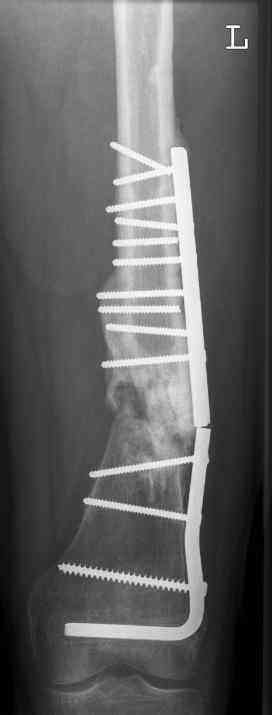

aug 06: blade plate + bone graft

nov 06: revision blade plate

feb 07: retrograde nail + bone graft + BMP

may 07: dynamisation nail

nov 07: persistant non-union distal femur; other fractures healed uneventfully.